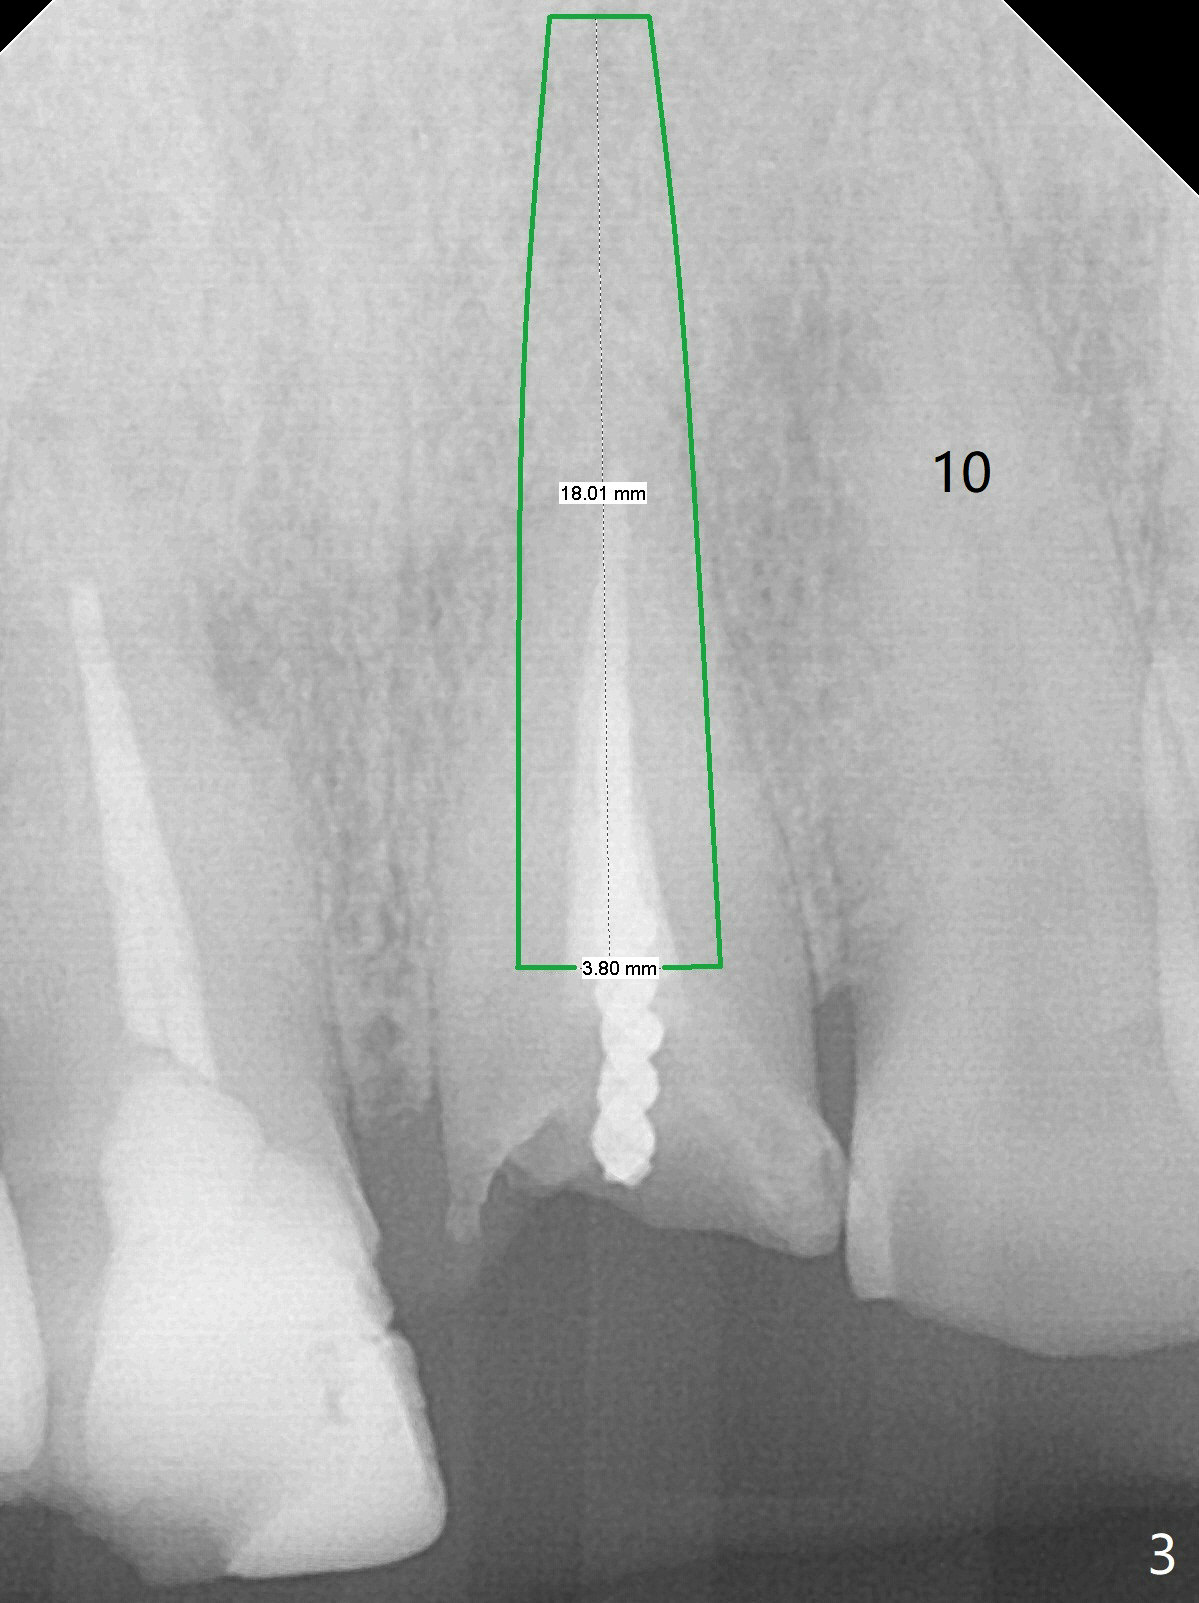

A 57-year-old man has history of fracturing post-RCT molar and difficulty in orthodontic intrusion. Now the tooth #9 fractures subgingival (Fig.1) with deep bite and heavy wear (Fig.2). A long implant will be placed to handle heavy occlusion and match the root length of the neighboring tooth (Fig.3 #10).